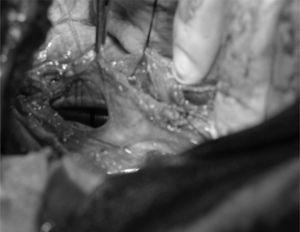

Se intervino a la paciente, y se evidenció un enfisema mediastínico, el neumobalón luxado en la rotura traqueal, localizado en la cara posterior y lateral derecha, desde el estrecho cérvico-torácico hasta 2 cm de carina (fig. 1). Se suturó y se reforzó la rotura con un colgajo intercostal, realizándose una nueva broncoscopia en el quirófano que dejó el neumobalón por encima del desgarro.

Figura 1. Reparación quirúrgica de la rotura traqueal.